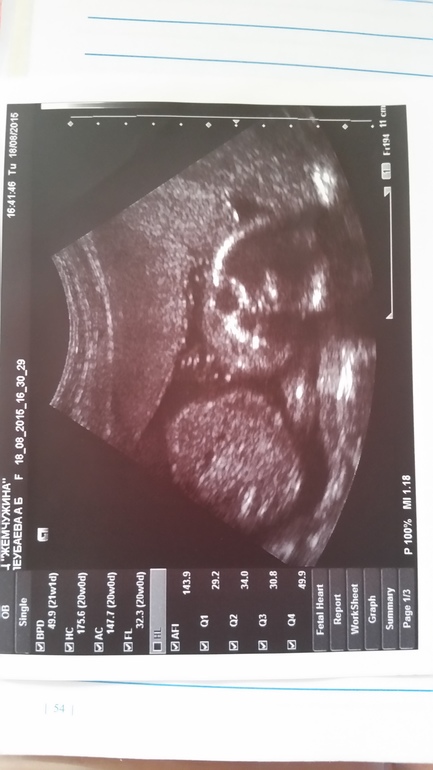

20 недель и узи. На память

Всё о нашей беременностиВот и посетили мы второй скрининг. Да, именно мы. Муж изьявил желание. Хотя до этого боялся идти :) С ребёнком все хорошо. Поставили ровно 20 недель. Исходя из этого узи начало срока совпало с началом стимуляции, т.е. 1 апреля. А подсадочка была у нас 17 апреля. Рассекретили наш пол :)) Девочка! Мы очень рады. Муж хотел дочку с самого начала говорил, что уверен что девочка. И я с детства думала, что у меня будет доченька. Никогда не представляла себя мамой мальчишки почему-то.

Есть и не очень моменты. Тонус не хороший, прямо у самого зева. И плацента низковата 30 мм. Поэтому поводу запереживала. Тонус внизу чувствую часто. Ещё и тянуло иногда как во время мес. За всю беременность впервые такое. Поеду в понедельник смотреть шейку. А то гинекологу все по фигу. Говорит все норм. За все время шейку ни разу не смотрели, что там вообще.

Малышка на узи крутилась без остановки. Даже фото сделать не давала. Не понравилось ей.

Фото на память :)